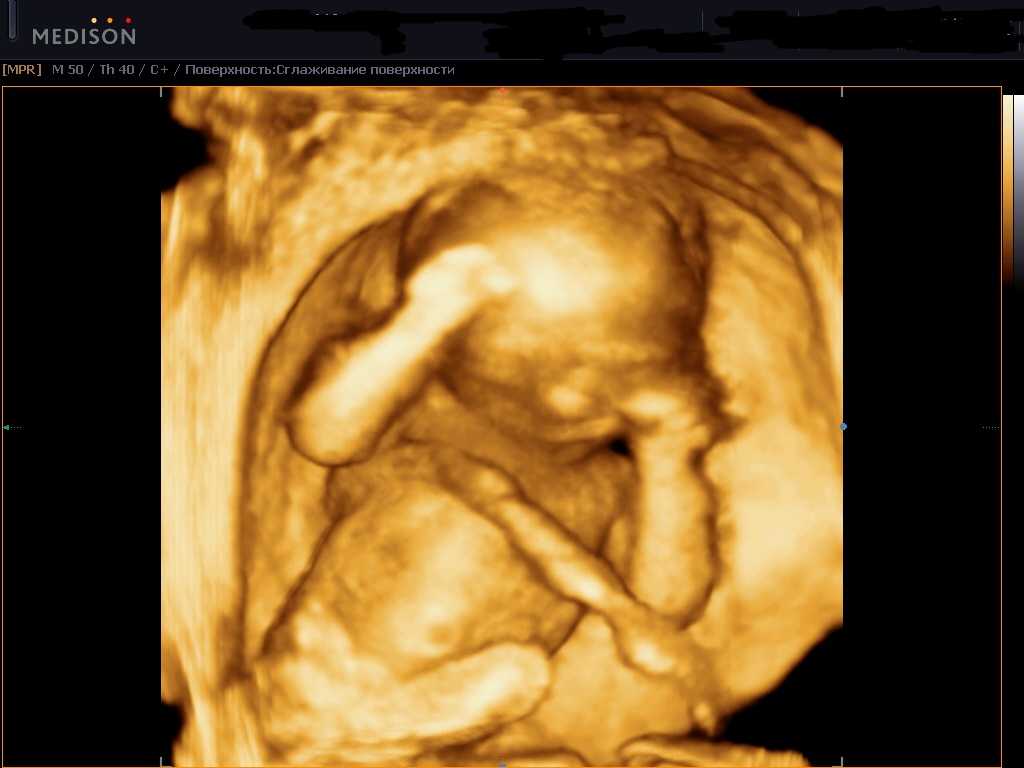

На этом сроке будущую маму могут отправить на третий скрининг. УЗИ плода на 29 неделе беременности от зачатия – обязательная часть обследования.

— Третий скрининг проводится для того, чтобы исключить патологические состояния течения беременности: фетоплацентарную недостаточность; внутриутробное отставание в развитии плода; кислородное голодание малыша (хроническая гипоксия); развитие внутриутробной инфекции; обвитие малыша пуповиной, преждевременное старение плаценты или ее предлежание, многоводие и маловодие, — объясняет врач акушер-гинеколог Олеся Побединская, pobedinskaya_81.

Чтобы убедиться, что кровоток в матке и плаценте не нарушен, проводится также доплерометрия.

Стоит отметить, что УЗИ на 29 неделе назначают редко, ведь плановое обследование третьего триместра проходят на 30-34 неделе. И все же будущей маме его могут назначить, если недавно она перенесла инфекционное заболевание.

Диагноз низкая плацента – еще одна причина УЗИ на 29 неделе беременности. Если есть подозрение на сокращение шейки матки, это может привести к выкидышу на поздних сроках.

Одной из важнейших задач УЗИ является выяснение предлежания плода. Обычно к этой неделе он занимает правильную позицию, но может до конца держать родителей в напряжении и поменять положение только перед родами.

Проверяют во время исследования и развитие ребенка, его фетометрию: бипариетальный и лобно-затылочный размеры, окружность живота и головы, длину самых крупных костей.

Что касается организма матери, то на УЗИ врач оценивает количество и качество амниотической жидкости как один из показателей нормы развития ребенка. Ее объем может говорить о работе почек малыша, а консистенция – о возможных инфекциях.

На 29 неделя беременности нет необходимости проводить УЗИ всем женщинам. Но иногда это исследования назначают при подозрении на патологию со стороны матери или плода.

УЗИ позволит установить соответствие развития плода сроку вынашивания

Особое внимание врач обращает на внутренние органы ребенка. При описании картины на экране обязательно учитывается степень зрелости плаценты и количество околоплодных вод. Параллельно выслушивается сердцебиение плода

В норме оно составляет 160-180 ударов на минуту

Параллельно выслушивается сердцебиение плода. В норме оно составляет 160-180 ударов на минуту.

При превышении этого значения врач может заподозрить кислородное голодание малыша. В таком случае дополнительно проводится доплеровское исследование пуповинного кровотока.

На данном этапе УЗИ исключит замершую беременность и покажет размеры матки, будет точно определен пол ребенка. Будущая мама сможет увидеть все органы малыша и получить снимок плода. Предлагаем вам посмотреть видео УЗИ плода на 29 неделе беременности, а также рассмотреть фото малыша выше.